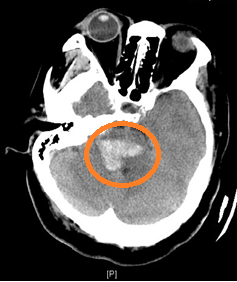

神经外科主要负责重症监护室(NICU)工作的副主任医师黄云峰介绍,患者入院时神志昏迷,自主呼吸微弱,需依赖气管插管呼吸机辅助呼吸,角膜反射等脑干反射均消失,CT显示脑干-小脑出血达10毫升,这种出血量属于重型脑干出血。“一旦脑干出血超过5毫升、病人昏迷,手术便成了最后一根救命稻草,同时,手术的风险也可想而知。”黄云峰说道。

图为CT显示患者大量脑干出血(黄色标注区域)